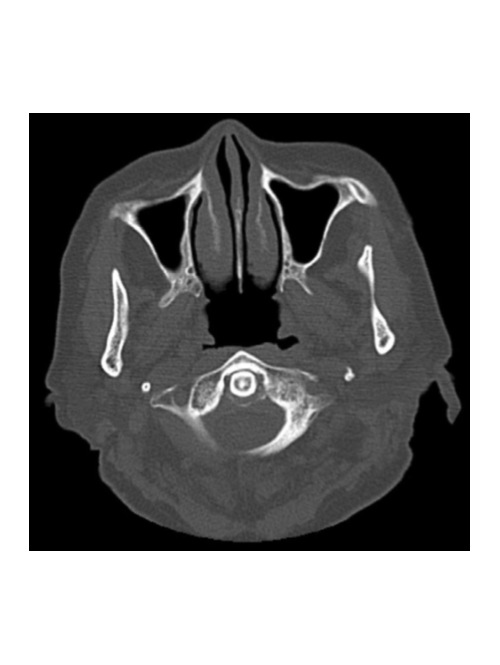

About four months after the treatment, the man went to hospital after his dentist referred him. A periapical x-ray revealed an infection and periapical osteolysis, and a cone-beam computed tomography (CBCT) scan revealed a complete sequestration of the interdental septum between teeth #46 and #47, as well as periapical osteolysis extending to the mandibular canal, the authors wrote.

The CBCT revealed the presence of sequestered bone between tooth #46 and tooth #47 (red arrow). The sequester is shown in coronal, sagittal, and axial views as well as in a 3D reconstructed view.